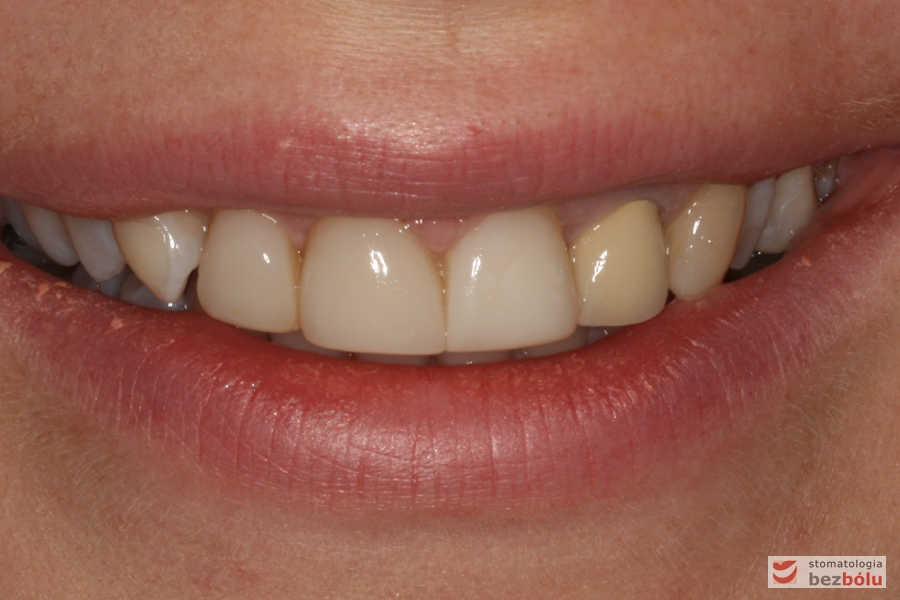

Pełny uśmiech pacjentki - niespójny kolor dwójki z pozostałymi zębami

Pełny uśmiech pacjentki – niespójny kolor dwójki z pozostałymi zębami